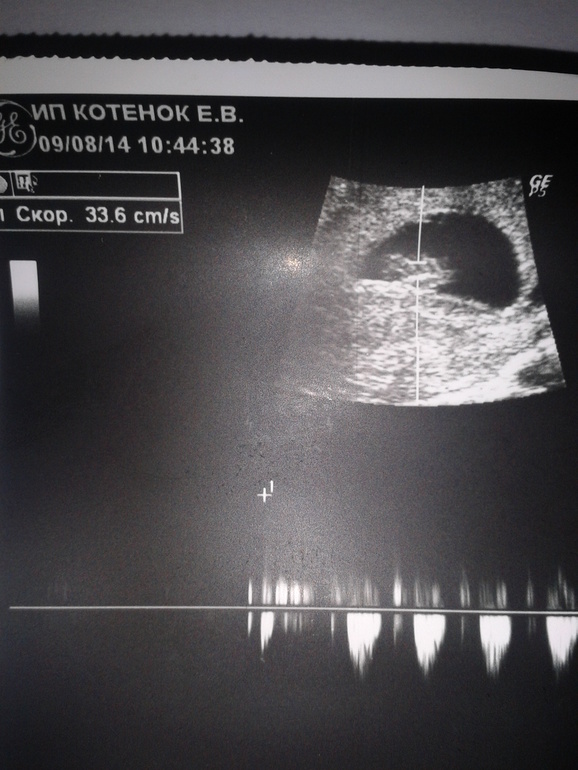

Попала на УЗИ в 8 недель и 3 дня от последних месячных:диаметр плодного яйца 38мм,КТР 20мм.Вроде все норм,и врач сказала плод растет и развивается.Вот только не указано ЧСС.И в заключении отмечено:сердечная деятельность эмбриона-определяется/не определяется(жирным выделено не определ.),и также движение эмбриона жирным выделено не определяется.Там этот протокол не рассматривала,доглядела уже дома.Вроде ж сердечко билось по ее словам,а почему же такое заключение?Да и первые спонтанные движения уже должны быть вроде...Или нет?и еще,может кто знает,что означает надпись в верхнем левом углу-скор.33,6см/с

График внизу на сколько я знаю и есть сердебиение, так уж оно есть, значит все хорошо))))

по месячным.Как я понимаю на фото ниже плода показано сердцебиение.Не в курсе?

Обычно к графику сердцебиения добавляют запись с частотой сердечного сокращения (ЧСС) и записывают количество ударов. Про то, что указано ниже плода, к сожалению не в курсе.Да и сердцебиению еще рано появляться. Точнее оно появляется на таком сроке, но абсолютно не у всех. У меня нашли в 7 нед 1 день от зачатия.